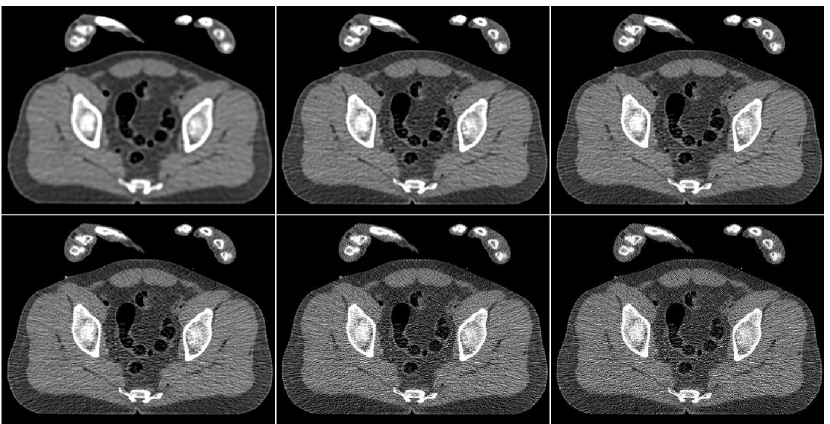

In order to test the robustness of the training results, we apply the ANN trained with the thigh sections, for a reconstruction of images of other body parts – sections of the head and the abdomen. Reconstruction results are presented in Figure 13 in the same order as in the previous comparison: middle image in the upper row is the result of fusion, which components are presented in the lower row. The head reconstruction is improved substantially by the fusion process, as visual observation shows. However, the SNR values (given in Table II) point to the favor of the PWLS image corresponding to iterations (lower middle image). The highest SSIM value does belong to the fusion result, though. In the case of the abdomen section, the fusion image is similar to the -iterations version but contains less noise; its quantitative measures are somewhat better than those of the individual PWLS images.

![]() |